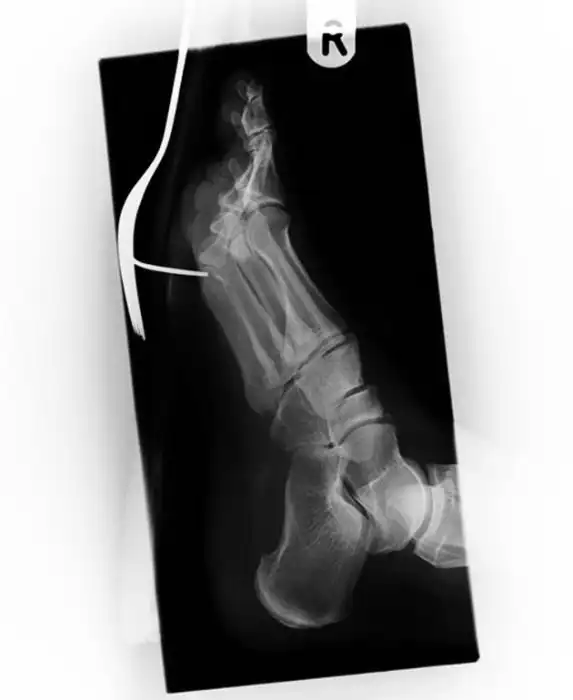

У меня тоже есть такой). Прошила палец на машинке, а кончик иглы вошел в кость пальца и сломался...

с оторванным пальцем уже не впечатляет, дурных детишек с такими травматическими ампутациями пальцев на работе насмотрелся и назашивался. Часть снимков с фатальными травмами. А с последней не понял. Ну тень средостения, ну загазованная толстая кишка, ничего патологического по костной системе не увидел, только в 10м межреберье слева хрень какая-то сеточкой.

Картинка с гвоздем в средней фаланге третьего пальца кисти похож на подделку, но кто знает может забил гвоздь по мягким тканям.